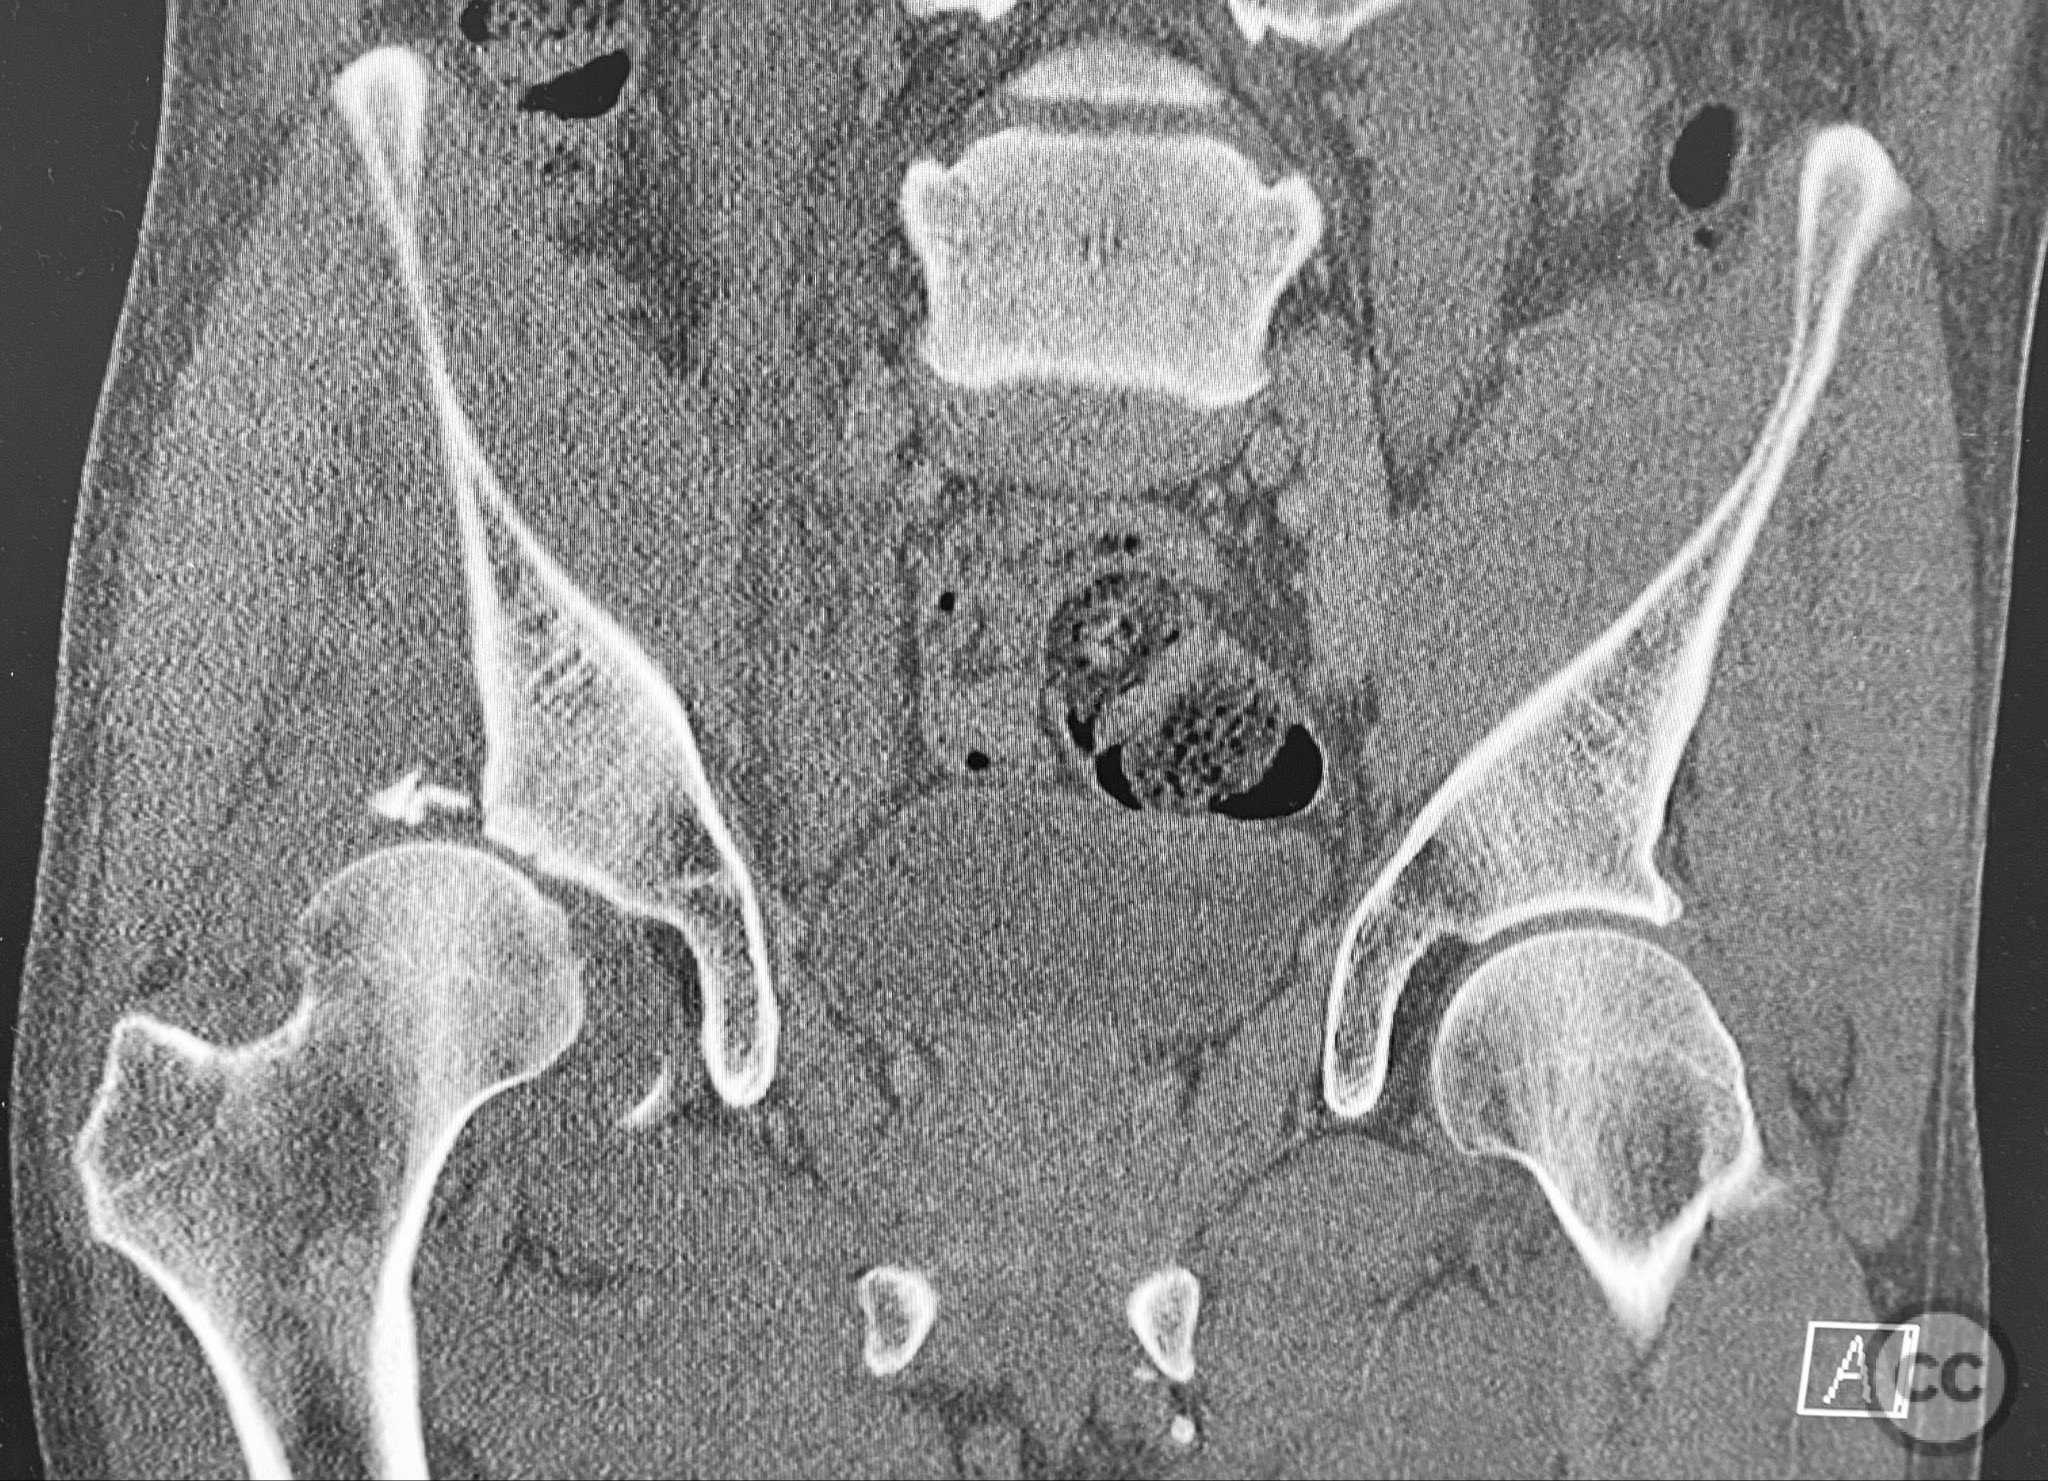

Clinical and radiological findings:  A middle-aged patient sustained a posterior wall acetabular fracture-dislocation, as demonstrated on initial AP pelvic radiograph. The film revealed a sizeable posterior wall fragment, cranial lateral impaction of the acetabular dome, and subtle deformation of the femoral head contour. Neurovascular examination was performed, including assessment of distal pulses and sciatic nerve function. The ipsilateral knee and anterior chest were examined for associated injuries (including possible knee ligamentous injury and thoracic trauma). An initial attempt at closed reduction under sedation was unsuccessful.

Planning remarks:  The preoperative plan included advanced imaging with CT, including 3D surface renderings, to further delineate the extent of articular impaction, wall fragment size, and comminution. The plan was for open reduction and internal fixation via a posterior Kocher-Langenbeck approach in the prone position. Elevation of impacted articular segments was planned, with structural support using autologous bone graft harvested from the greater trochanter. Fragment-specific fixation was planned with a spring hook plate for the cranial wall fragment and a reconstruction plate for the main posterior wall fragment.

The initial failed closed reduction likely resulted from interposed soft tissue or bony fragments, or inadequate sedation/muscle relaxation. Repeat reduction under improved conditions was successful prior to definitive fixation. 3D CT renderings provided enhanced visualization of impaction zones and comminution, facilitating preoperative planning for grafting and fragment-specific fixation. Intraoperatively, elevation of the impacted dome required careful manipulation to avoid further chondral injury. Use of a spring hook plate provided secure fixation of the cranial wall fragment, while the reconstruction plate supported the main wall fragment. Postoperative CT confirmed satisfactory reduction and implant positioning.